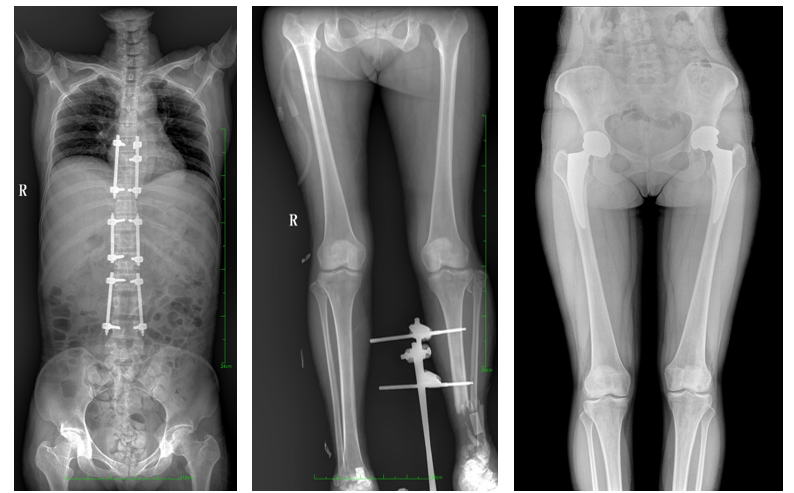

普愛醫(yī)療自主研發(fā)的一款數(shù)字化X光機(jī)——PLX8600大視野平板動(dòng)態(tài)DR,擁有43cm*86cm超大有效視野,可一次性拍攝全脊柱、雙下肢的影像視野。使全脊柱及雙下肢能夠得到完整清晰的成像,為臨床在脊柱側(cè)彎畸形和下肢骨關(guān)節(jié)病變診斷、治療方案制定及治療后復(fù)查提供精準(zhǔn)的測量。

除常規(guī)靜態(tài)攝影外,PLX8600具備動(dòng)態(tài)透視和點(diǎn)片功能,透視采集功能可支持大視野、多角度的可視化觀察。通過可視化的動(dòng)態(tài)影像,配合點(diǎn)片功能,能夠很好的觀察復(fù)雜部位病灶,有效的抓取關(guān)鍵幀,降低患者多次攝片的概率。如:全脊柱狀態(tài)評估、長骨關(guān)節(jié)活動(dòng)度、下肢靜脈造影瓣膜功能評估、消化道功能評估、脊髓造影等更多大視野臨床應(yīng)用。